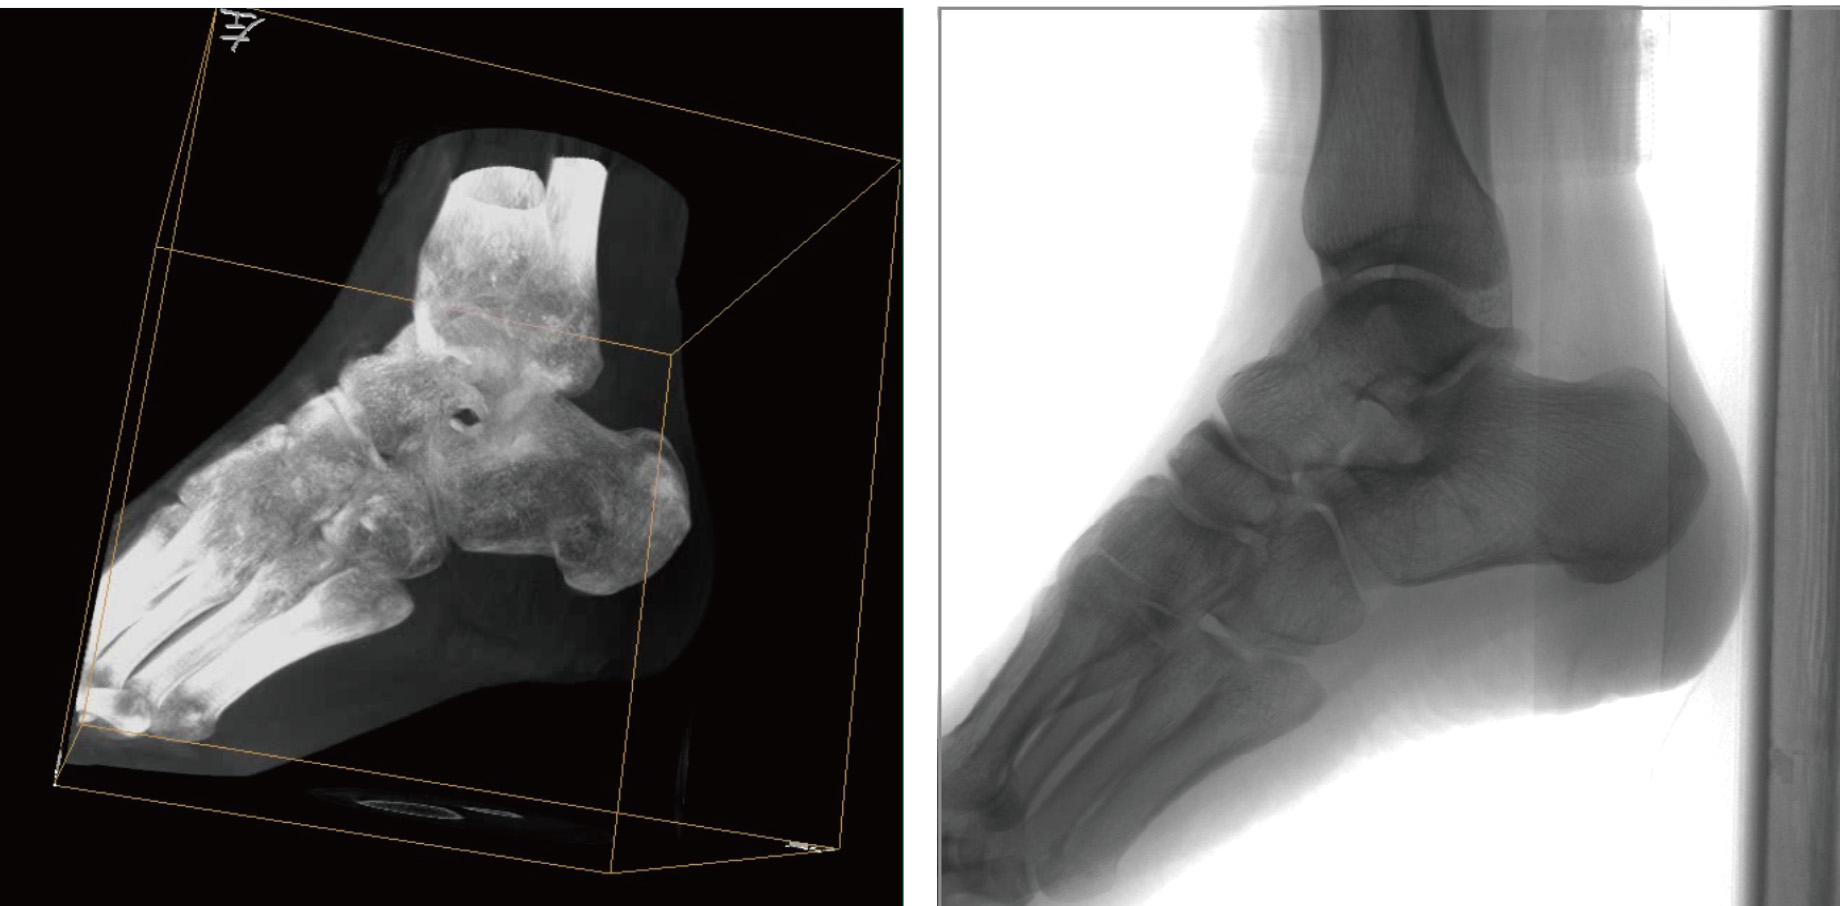

骨科三維C形臂透視導航已在骨科手術中得到廣泛,極大優點就是術者可以在術中實時獲得患者三維重建的圖像,可以根據二維圖像和三維圖像的對比來實現手術的微創和準確性,且術者還可以在術中根據實際情況隨時改變手術治療的方案,而不必過多地擔心定位不準確帶來的一系列問題。

普愛醫療天弓PLX7500骨科三維C形臂,作為“術中CT”,在手術中快速生成類CT斷層圖像和立體三維圖像,為醫者提供更全面的圖像信息,能夠準確地觀察植入物的情況,例如螺釘內固定術入釘的位置和角度。天弓PLX7500三維C形臂性能特點:

PLX7500骨科三維C形臂通過采集,能在術中快速地生成橫斷面、矢狀面、冠狀面和可旋轉的立體圖像,給術者提供360°無死角的觀察角度,準確判斷骨組織和植入物的情況,為手術的實施提供保障,極大提高手術成功率,減少并發癥概率。

天弓PLX7500骨科三維C形臂影像